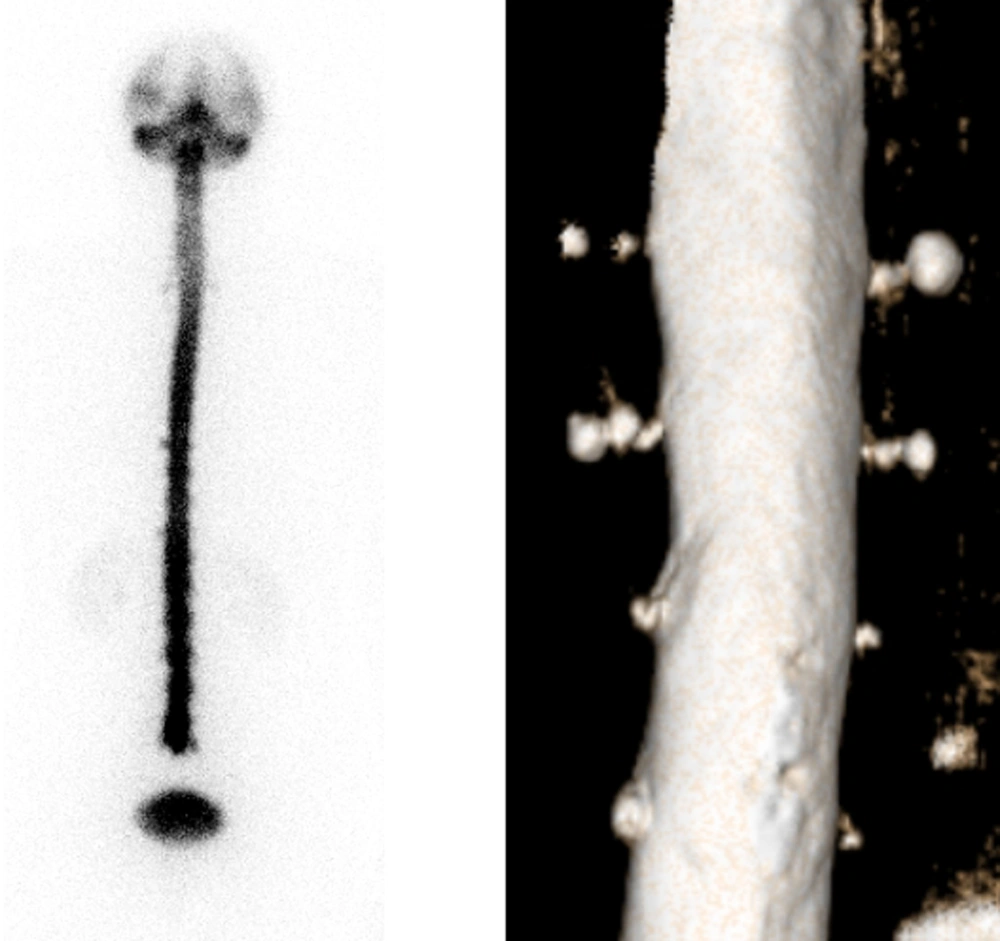

We fully agree with Lu and colleagues that direct signs of leakage should be always looked for in RNC, as early appearance of bladder radioactivity is an unreliable indirect sign, probably due to traumatism after lumbar puncture. This was elegantly shown by Takahashi et al. (2) and subsequently confirmed by others. However, in our opinion, the images of increased radioactivity showed by Lu et al. symmetrically distributed on both sides of the spinal canal, should not be regarded as direct signs of leakage. Rather, these images might correspond to prominent structural abnormalities such as meningeal diverticula or nerve root cysts. These anatomical variants together with any other structural meningeal weaknesses, are known to confer an increased risk of CSF leaks, potentially requiring corrective surgery (3). When the patient stands up, CSF is likely to spread to the loci of least resistance, not seen in the supine position. Correlative radiological imaging would be needed to show underlying anatomical abnormalities. In Figures 1 and 2 we give an example of that.